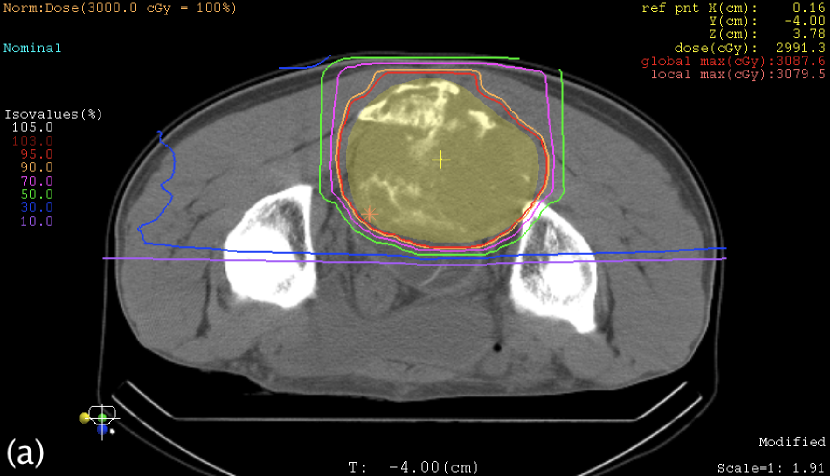

III.3 Case study

Table 3 shows the maximum WE thicknesses of the range compensators. Except for the posterior beam in the sacrum case, range compensation was large as it had been expected for oblique-incident beams. Figures 4 and 5 show the plan dose distributions, in which the reduction of clinical dose was 0.30% at the isocenter in the sacrum case, 0.75% at the isocenter in the nose-and-sinus case, and mostly within 1% in these targets. In the nose-and-sinus case, the dose reduction greater than 2% occurred only in the air that happened to be included in the dose-calculation volume. Relatively speaking, the dose reduction was greater in the posterior part of the sacrum target and in the anterior-left (away from nose) part of the nose-and-sinus target, which was caused by locally shallower target depth and hence larger range compensation in the fields.